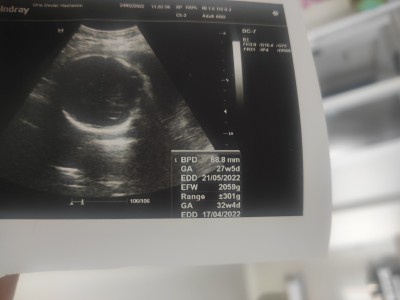

EFW kilosu mu acaba bide 32 W yazıyı o haftası mi oluyo bebeğim 26 haftalık 1 kiloydu geçen hafta

2059 g, 27 hafta 5 günlük görünüyor. Ga son adet tarihine göre oluyor.

Evet bebeğin ağırlığı efw oluyor bildiğim kadarıyla üstteki ga bebegin ne kadarlık olduğu 27 hafta 5 günlük

EDD yani son adet tarihine göre 27 hafta 5 günlük ama FDD yani ultrason ölçümüne göre 32 hafta 4 günlük. Bebek 2059 gr ama bu değerin 300 gr kadar yanılma payı var diyor.